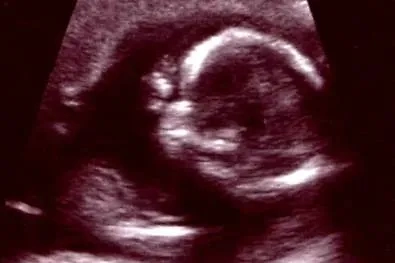

Близнец-паразит — это аномалия развития плода, битва, которая происходит в утробе матери. Фото © Wikipedia / colors.life

Это не то чтобы болезнь в прямом смысле этого слова, но качество жизни ишиопаг роняет сильно. Близнец-паразит — это не фильм ужасов, а редчайший биологический феномен, который встречается как у людей, так и у животных. В утробе матери развиваются два близнеца, но один из них оказывается жизнеспособнее. Его тело буквально «съедает» соперника. В итоге рождается только один из них, но маленькие части тела могут всё ещё находиться на теле «счастливчика». Например, в 2005 году в Индии родилась Лакшми Татма, девочка с четырьмя ногами и четырьмя руками. Две пары из них как раз принадлежали близнецу-паразиту. Через два года за 27-часовую операцию их удалось разделить. Ребёнка назвали в честь богини богатства Лакшми, так как именно у этого божества восемь конечностей. Бедную девочку пытались сделать объектом поклонения местные селяне, а сотрудники бродячего цирка хотели украсть её у матери.